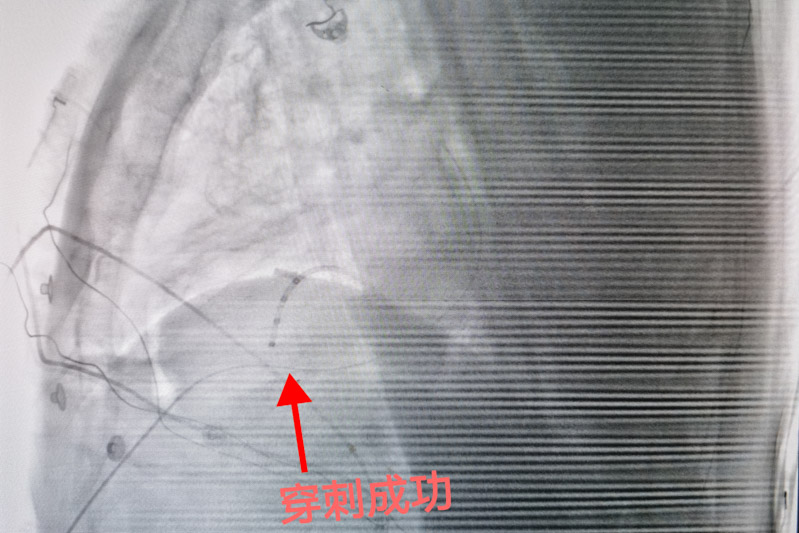

心外膜室性心動過速行射頻消融術(shù)這項技術(shù)是心包腔內(nèi)無積液的情況下,經(jīng)胸壁進(jìn)行干性穿刺后,將標(biāo)測及消融導(dǎo)管送到心包腔內(nèi),再進(jìn)行定位消融異常的心電病灶,手術(shù)風(fēng)險大、標(biāo)測復(fù)雜、技術(shù)難度高,需要團(tuán)隊具備極高的心包穿刺及導(dǎo)管操作技術(shù)。

為確保手術(shù)安全,心血管內(nèi)科電生理團(tuán)隊準(zhǔn)備了詳盡的手術(shù)方案和應(yīng)急預(yù)案。手術(shù)當(dāng)日,北京安貞醫(yī)院心血管內(nèi)科蔣晨曦教授親臨指導(dǎo),在ICE及X線引導(dǎo)下,精確地將導(dǎo)絲通過心包干性穿刺途徑到達(dá)心外膜,再通過動靜脈途徑到達(dá)心內(nèi)膜,采用心內(nèi)膜聯(lián)合心外膜進(jìn)行標(biāo)測及消融。放電3秒后室性心動過速終止,鞏固消融120秒,并在靶點附近鞏固放電多次,經(jīng)過一段時間觀察,無室性心動過速再發(fā),手術(shù)順利結(jié)束。術(shù)后患者癥狀解除,復(fù)查動態(tài)心電圖顯示無室性心律失常再發(fā),目前陶先生已成功康復(fù)出院,門診隨訪也一切良好。